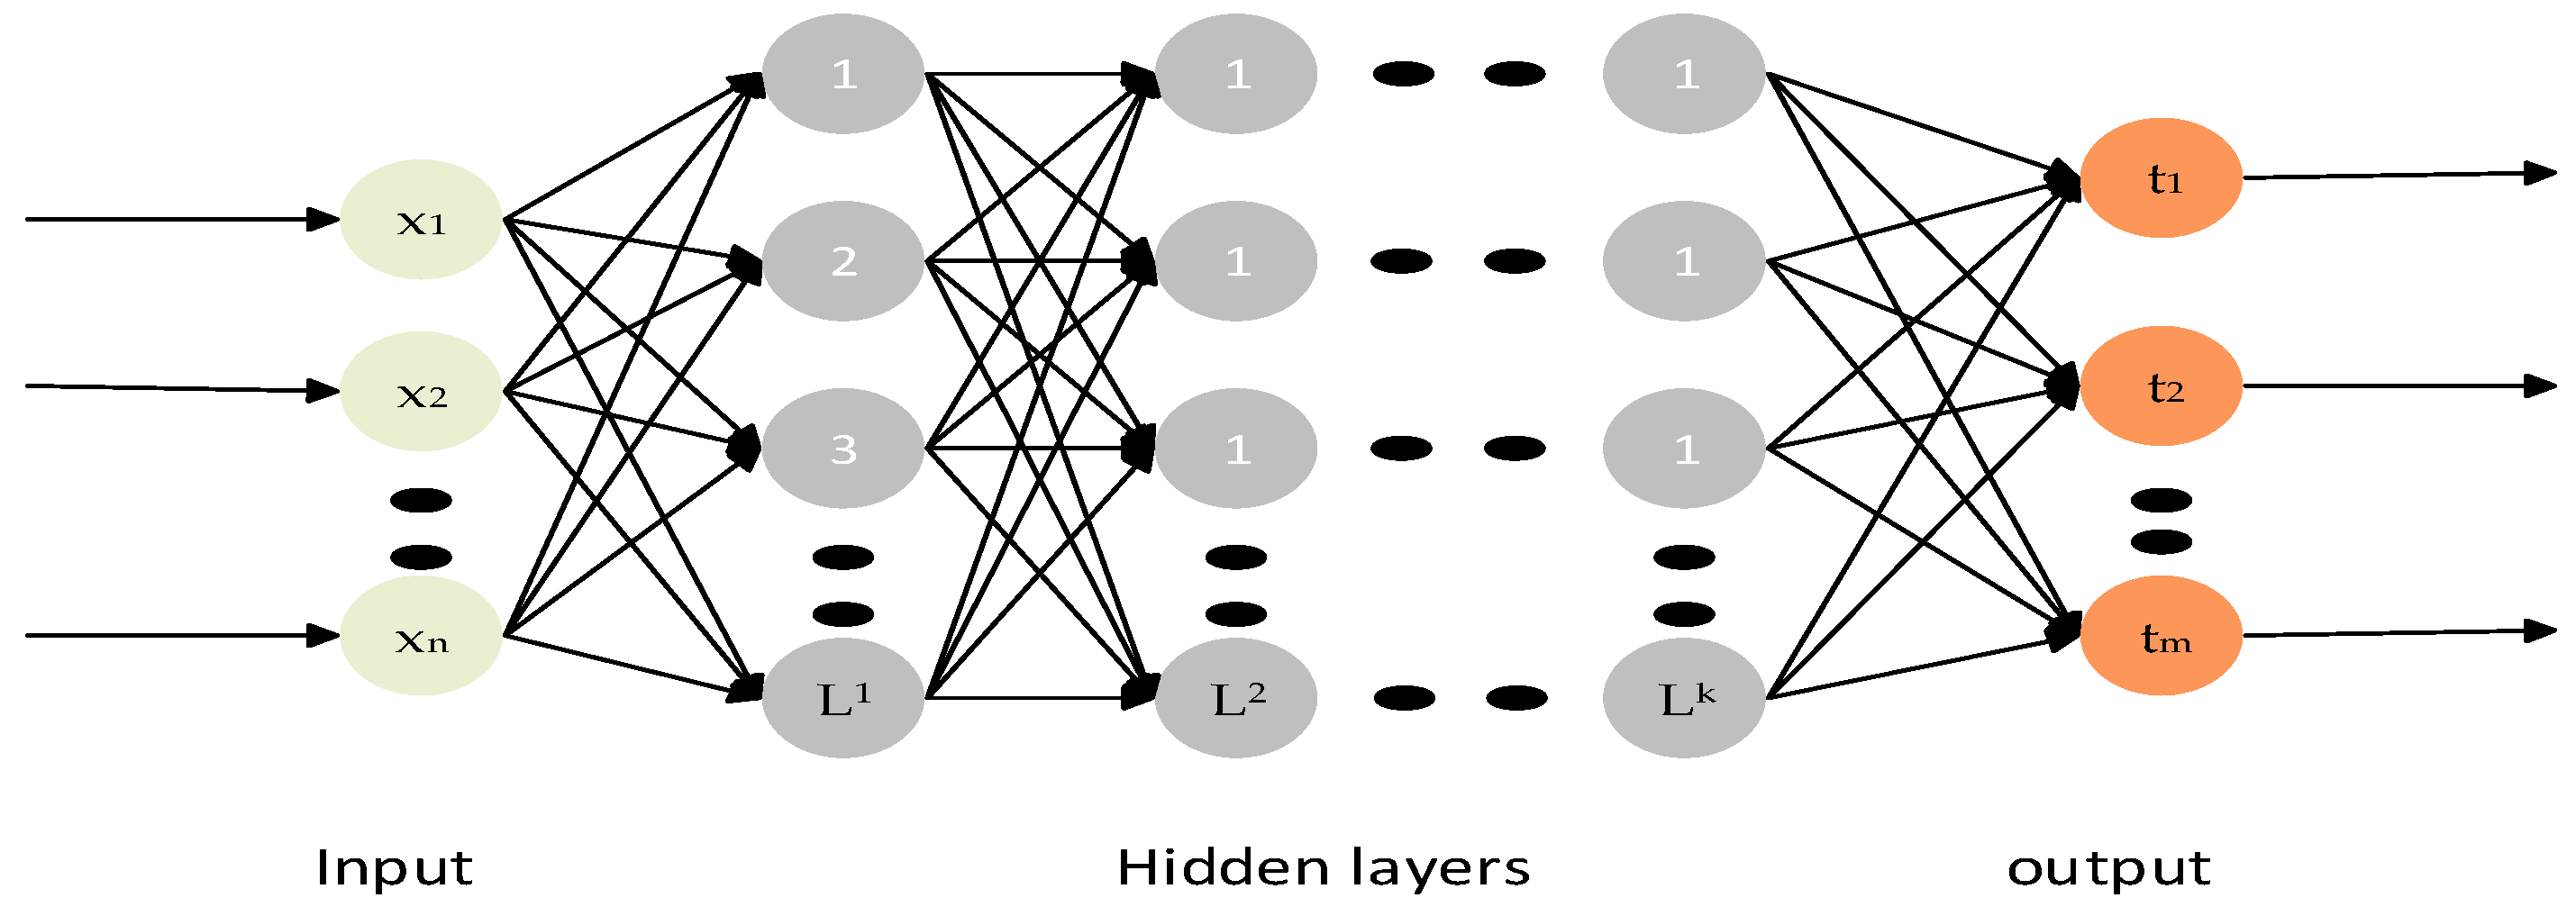

2.6. Classifiers

- Qureshi, M.N.I.; Min, B.; Jo, H.J.; Lee, B. Multiclass Classification for the Differential Diagnosis on the ADHD Subtypes Using Recursive Feature Elimination and Hierarchical Extreme Learning Machine: Structural MRI Study. PLoS ONE 2016, 11, e0160697. [Google Scholar] [CrossRef]

- Zhang, W.; Shen, H.; Ji, Z.; Meng, G.; Wang, B. Identification of Mild Cognitive Impairment Using Extreme Learning Machines Model. In Intelligent Computing Theories and Methodologies; Huang, D.-S., Jo, K.-H., Hussain, A., Eds.; Springer International Publishing: Cham, Switzerland, 2015; pp. 589–600. [Google Scholar]